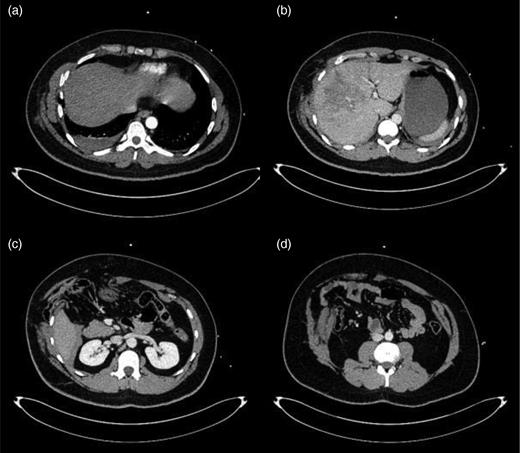

Trauma series computed tomography (CT) scans demonstrated a flail segment between the sixth and eight ribs with disruption of the intercostal muscles and a small right haemothorax (Fig. 1a). In the abdomen, there was hepatic contusion with an intrinsic liver injury (Fig. 1b). Blood was noted around the liver with minor active haemorrhage. The right abdominal wall was ruptured—the right rectus abdominis muscle had been torn from its costal attachments to the midpoint. The hepatic flexure of the colon had herniated through the intercostal muscles of the eighth and ninth ribs and was lying adjacent to the fractured ribs (Fig. 1c). Both small and large bowel had herniated through the abdominal wall lateral to rectus abdominis, but remained covered by external oblique (Fig. 1d). Herniation of small and large bowel immediately adjacent to the fractured ribs raised the suspicion of occult bowel injury not detected on CT.

(a–d) Initial CT imaging performed as part of the secondary survey.